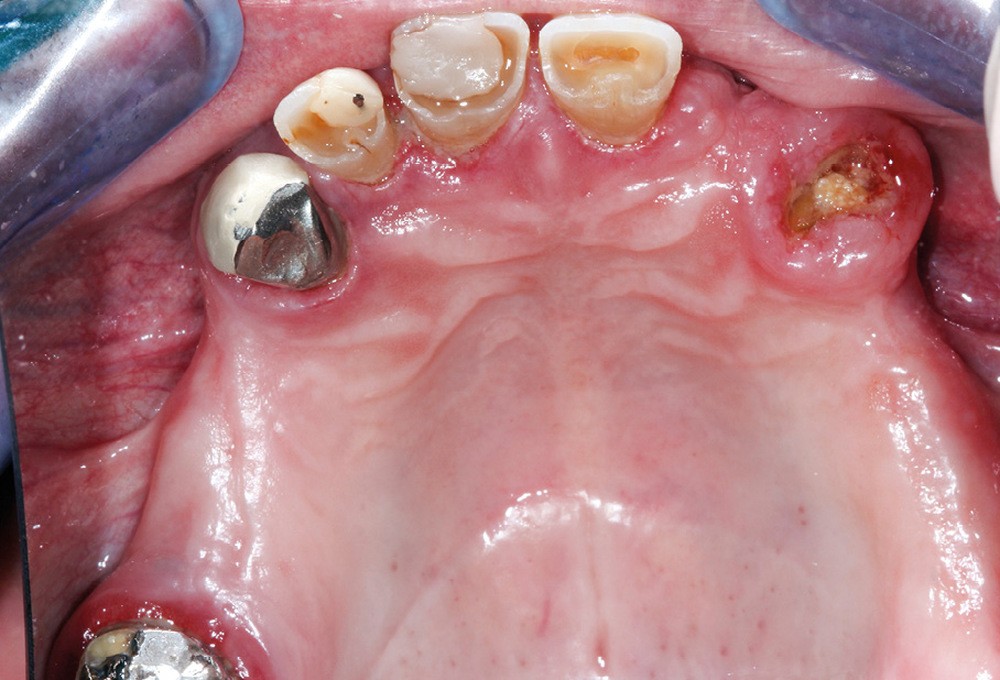

Réévaluation (mars 2022)

Le patient a été satisfait de l’immédiateté et du confort de la restauration provisoire, mais n’a malheureusement pas poursuivi son traitement et n’est venu consulter que quelques années plus tard, avec des répercussions prévisibles et néfastes. L’absence de calage molaire, l’hygiène déficiente (aucun passage de brossette dans les embrasures) et une absence de suivi au cabinet ont entraîné une inflammation très importante des tissus péri-implantaires (fig. 8…